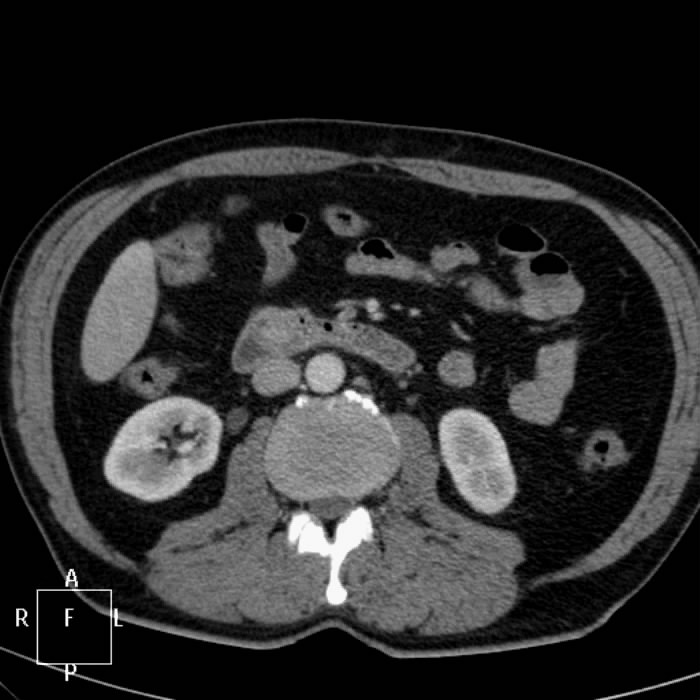

Фотографии медицинских исследований инсулиномы и синдрома Триады Уиппла